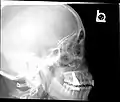

X-ray images and illustrations

Paranasal sinuses radiograph (lateral)